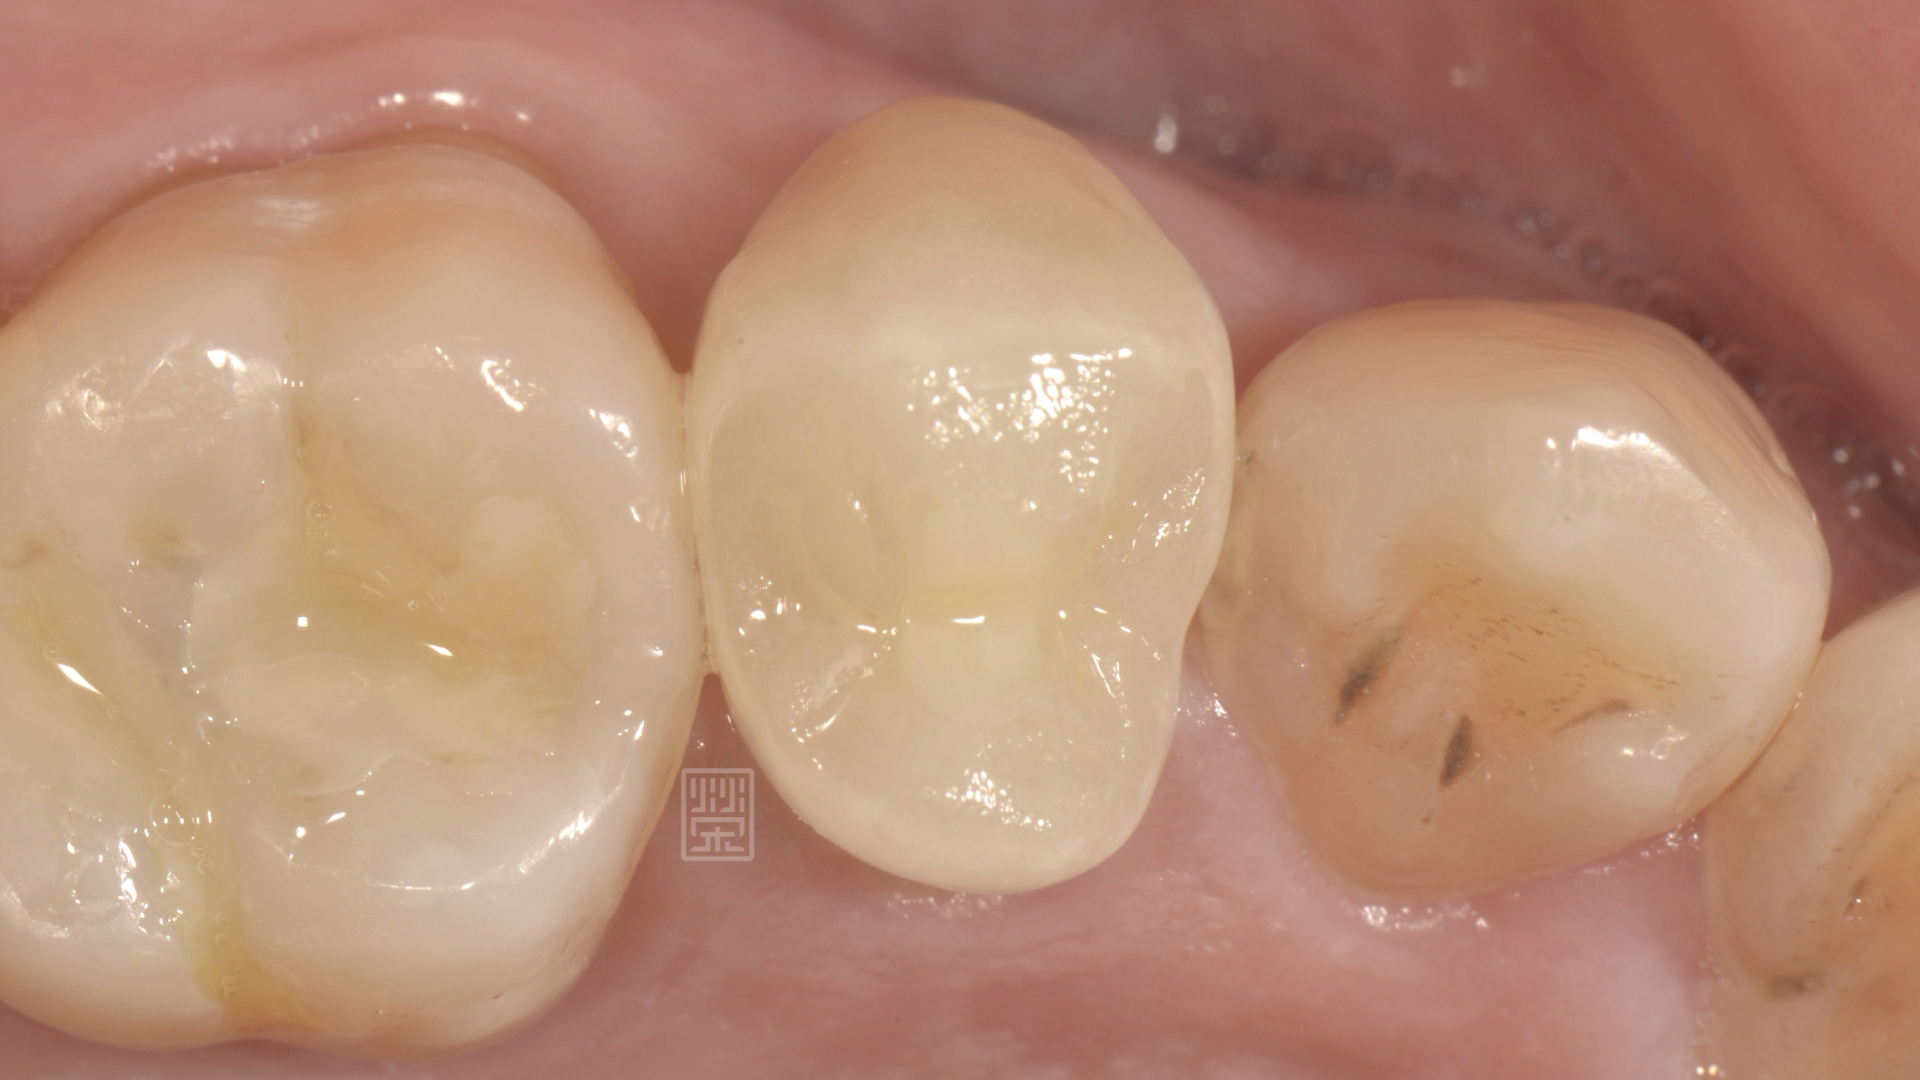

蛀牙拿乾淨後,很像蘋果卡通圖被啃一圈的樣子

另一個角度看清除蛀牙後的狀況

全瓷嵌體修復治療完成